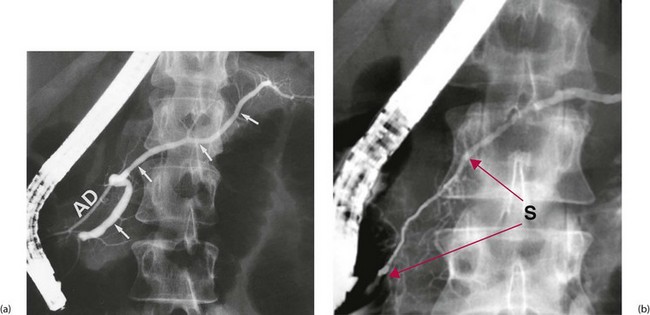

image

Fig. 25.3 Retrograde pancreatography

These films were both obtained by injecting contrast into the pancreatic duct using a flexible duodenoscope. (a) This pancreatogram is normal. The main duct (arrowed) narrows regularly towards the tail of the pancreas and there are no strictures or dilatations along its length. The accessory pancreatic duct AD also fills in this patient. (b) This pancreatogram is from a man of 26 with a history of severe upper abdominal pain. There is a long stricture of the main duct between the red arrows S of unknown origin. Typical changes of chronic pancreatitis, i.e. irregularity of the wall with dilatations and poor filling of small ducts, are seen in the duct distal to the stricture